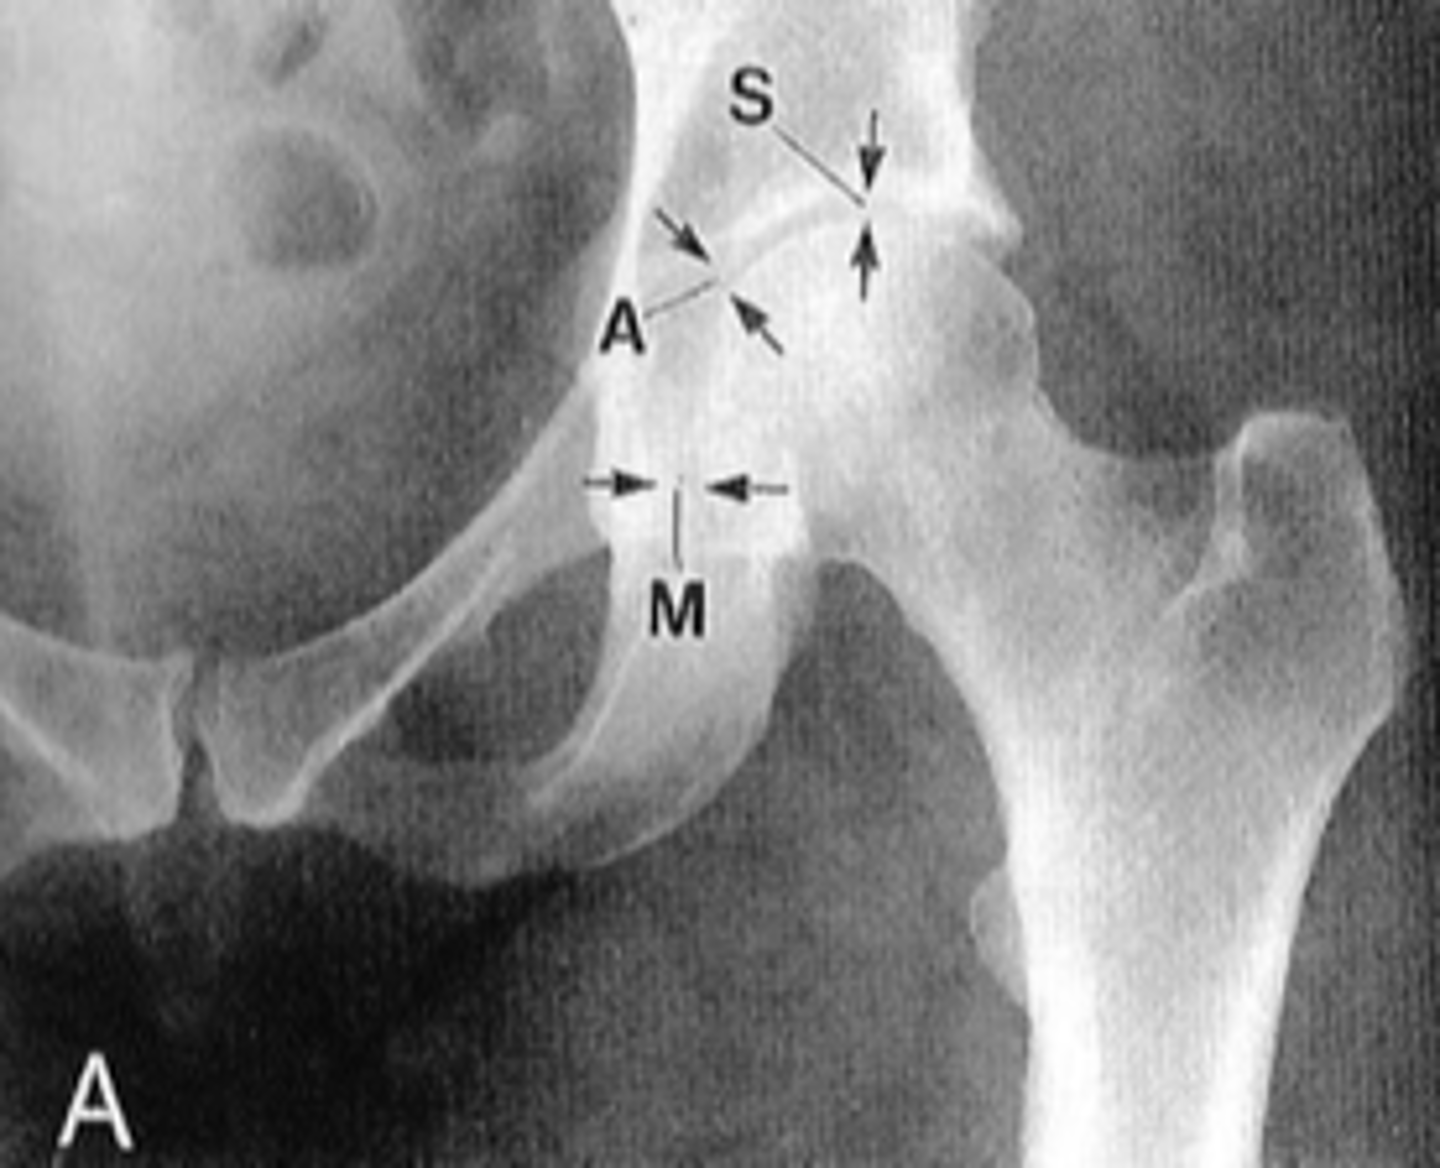

Left femoroacetabular joint

ID 2 (joint)

<p>ID 2 (joint)</p>

Right: gluteus medius

Left: gluteal fat stripe

ID 5

<p>ID 5</p>